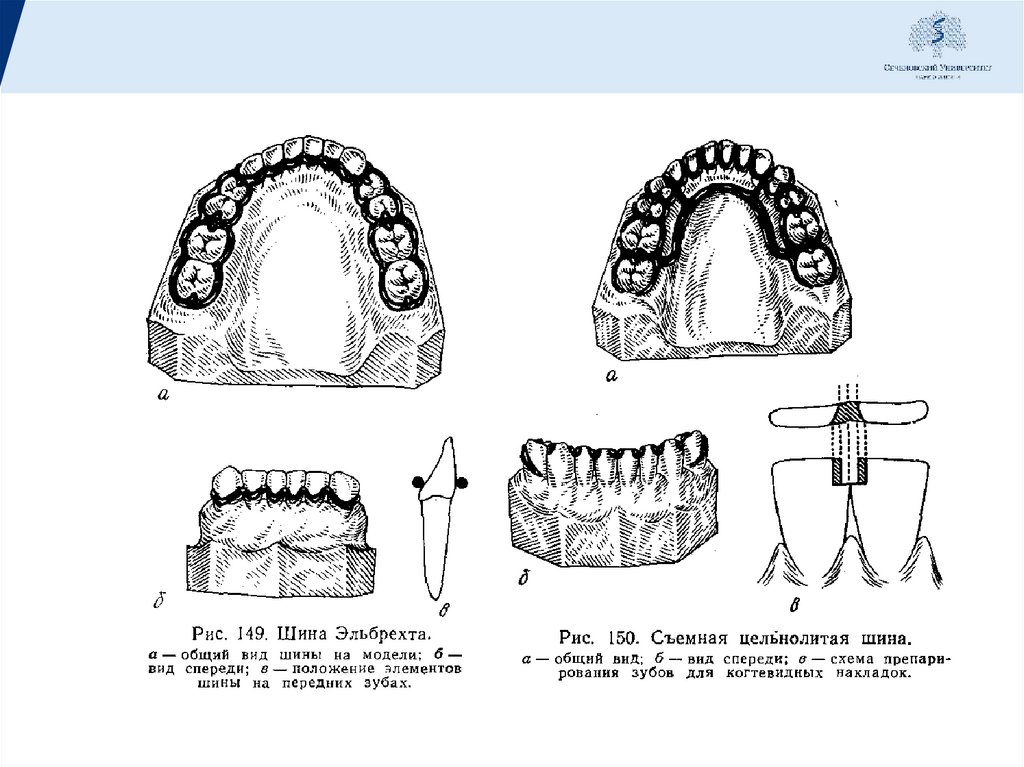

• Шина Эльбрехта. Сплав каркаса эластичный, но достаточно

прочный. Это обеспечивает защиту от подвижности зубных

рядов во всех направлениях, кроме вертикального, т.е. не

дает защиты при жевательной нагрузке.

• Шина Эльбрехта с т-образными кламмерами в области

передних зубов. Такая конструкция позволяет добиться

дополнительной фиксации зубной дуги. Однако эта

конструкция годиться лишь при минимальной подвижности

зубов и отсутствии выраженного воспаления пародонта,

54.

• Съемная шина с литой каппой. Это модификация шины

Эльбрехта, позволяющая снизить подвижность резцов и

клыков в вертикальном (жевательном) направлении. Защита

обеспечивается наличием специальных колпачков в области

передних зубов, которые и снижают жевательную нагрузку на

них.

• Круговая шина. Она может быть обычной или с

когтевидными отростками. Используется при невыраженной

подвижности зубов, т.к. значительное отклонение зубов от

своей оси приводит к сложностям при попытке надевания

или снятия протеза.